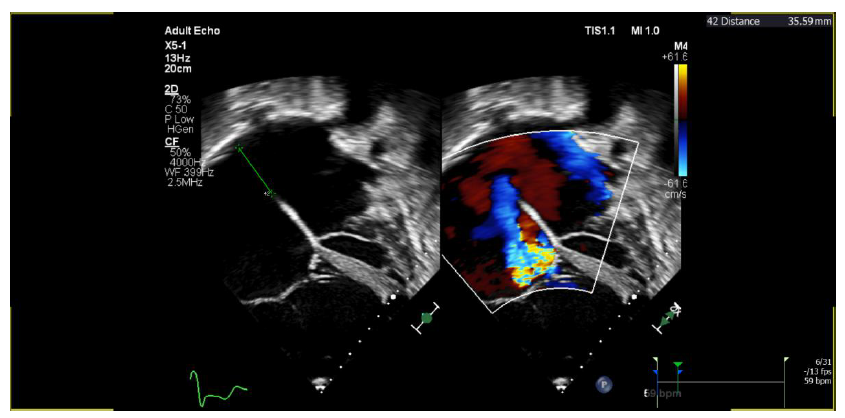

Gambar Echo pasien

Kasus: Laki laki usia 55 tahun dengan kasus hernia inguinalis lateralis dekstra reponible dengan ASD dan hipertensi pulmonal derajat sedang. Pasien dilakukan insersi epidural kateter di L4-L5 setelah di konfirmasi dengan loss of resistance dengan saline dan test dose. Regimen epidural yang diberikan bupivacaine 0,25% + lidocaine 1% volume 10 mL. Intraoperatif diberikan titrasi norepinephrine dengan dosis titrasi 0,15-0,3 mcg/kgBB/menit dan tirasi dobutamine 2,5-5 mcg/kgBB/menit. Pengobatan postoperatif analgesia pengobatan epidural bupivacaine 0,0625% + morfin 0,5 mg volume 10 mL tiap 12 jam, dan parasetamol 500 mg tiap 6 jam tablet untuk obat analgesia.

Pembahasan: Teknik anestesi epidural dipilih karena memiliki onset yang lebih lama dan hemodinamik variasi yang lebih kurang dibandingkan dengan teknik anestesi spinal atau kombinasi teknik spinal-epidural. Sedangkan teknik general anestesi tidak dipilih karena berisiko terhadap resistensi vaskular pulmonal dan dapat mengubah arah shunting. Prinsip dari penanganan ASD adalah untuk mempertahankan cardiac output dan menghindari adanya penurunan dari resistensi sistemik vaskular. Mempertahankan resistensi sistemik vaskular berdsarkan dengan mean arterial pressure sehingga menghindari adanya perubahan arah shunt.